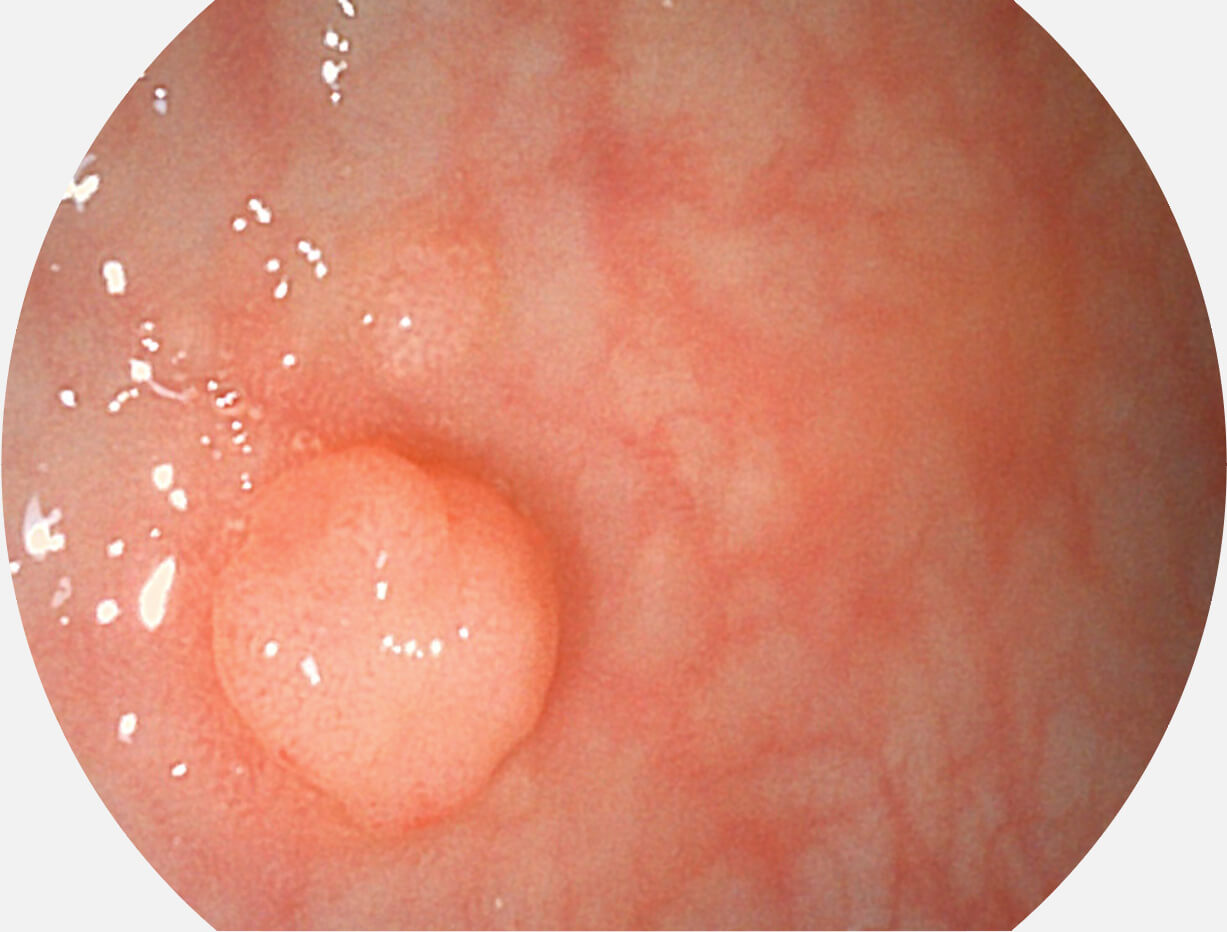

白光图像

SFI图像

图像具有高亮度、高黏膜血管颜色对比度的特点,且不改变粘液、食物残渣、粪便的基本颜色,可在中远景下进行观察,助力消化道早期疾病的诊断。

采用光路合束技术,光谱自由度高,实现了更丰富的照明模式,染色模式SFI及VIST,从远景到近景,助力消化道早期疾病诊断。